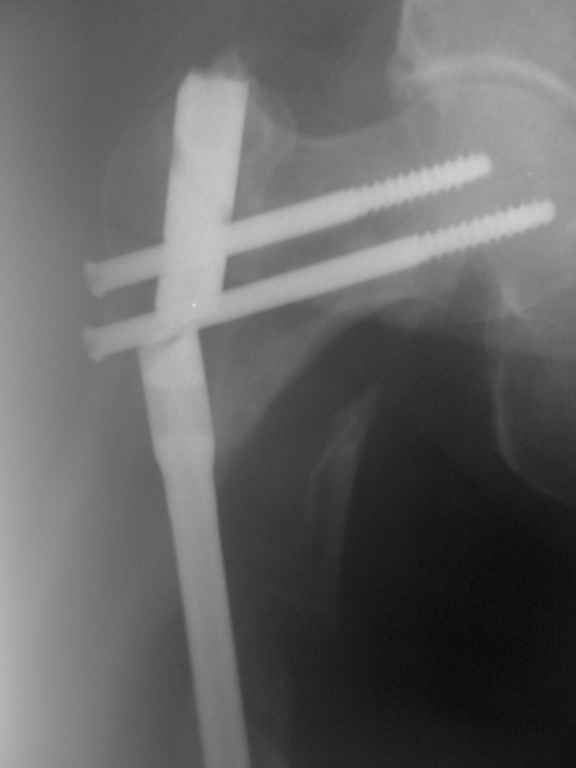

Пациентка 69 лет. травма в ДТП год назад. оскольчатый перелом бедра. выполнен остеосинтез штифтом. 2 недели назад вставая с постели почувствовала резкую боль в области перелома.

Р-гр в приложении.

в анамнезе: ИБС. атеросклеротический кардиосклероз. пароксизмальная форма фибриляции и трепетания предсердий. артериальная гипертония. риск ССО4. ЦВБ. дисциркуляторная энцефалопатия. железодифицитная анемия. тромбофлебит большой подкожной вены слева. посттромботическая болезнь обеих нижних конечностей. нейропатия малоберцового нерва справа. ожирение 3 степени.

Другая нижняя конечность в связи с неправильно сросшимся переломом мыщелков большеберцовой кости не полностью опороспособна.

вес +\-140 кг.